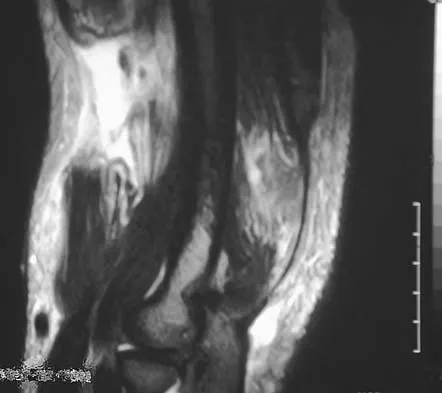

A 21-year-old man has mild but persistent aching pain in his left proximal thigh during impact loading activities. He denies pain at rest and has no other symptoms. Figures 34a through 34e show the radiographs and T1-weighted, T2-weighted, and gadolinium MRI scans of the left hip. What is the most likely diagnosis?

Explanation

A 21-year-old man has had right groin pain for the past year. A radiograph, CT scan, MRI scans, and a biopsy specimen are shown in Figures 50a through 50e. What is the most likely diagnosis?

Explanation